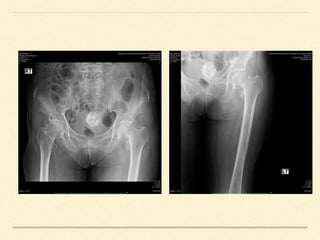

IMAGING

Radiographs

• ภาพรังสีท่าตรง(Femur AP)และท่า lateral cross table ช่วยการวินิจฉัย โดยพบความไม่ต่อเนื่องของ Shenton

line แต่ใน incomplete fracture รอยหักอาจไม่ชัดเจนในท่าตรง ภาพรังสีในท่าบิดสะโพกเข้าด้านในจะช่วยทาให้เห็น

รอยหักชัดเจนมากขึ้น ฉายรังสีตั้งฉากกับกระดูกต้นขา เพื่อให้ได้ภาพรังสีในแนวด้านข้าง โดยไม่ขยับสะโพกด้านที่บาดเจ็บ

IMAGING Radiographs • ภาพรังสีท่าตรง(Femur AP)และท่าlateral cross table ช่วยการวินิจฉัย โดยพบความไม่ต่อเนื่องของ Shenton line แต่ใน incomplete fracture รอยหักอาจไม่ชัดเจนในท่าตรง ภาพรังสีในท่าบิดสะโพกเข้าด้านในจะช่วยทาให้เห็น รอยหักชัดเจนมากขึ้น ฉายรังสีตั้งฉากกับกระดูกต้นขา เพื่อให้ได้ภาพรังสีในแนวด้านข้าง โดยไม่ขยับสะโพกด้านที่บาดเจ็บ